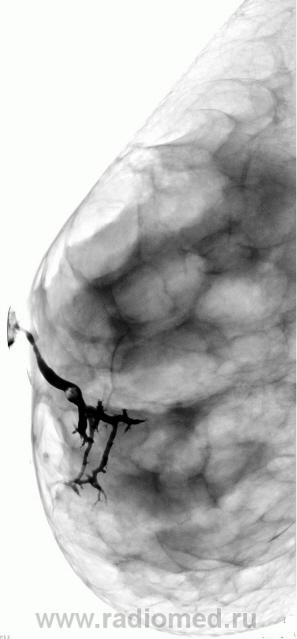

Случай 2.  Внутрипротоковое образование.   Случай Рыбаковой Л.А.

Пациентка предъявляет жалобы на наличие кровянистых выделений из протоко правой молочной железы в течение года. Проведено УЗИ, патологии не выявлено. Взяты мазки- отпечатки. Пациентка направлена "на дуктографию". Бужирован проток, с трудом введено 0,7 мл. контрастного вещества. Контрастирован проток в нижне-внутреннем квадранте правой молочной железы. Центральный проток равномерно расширен, определяется внутрипротоковое образование, контуры его ровные, чёткие. Данное образование практически обтурирует просвет протока.